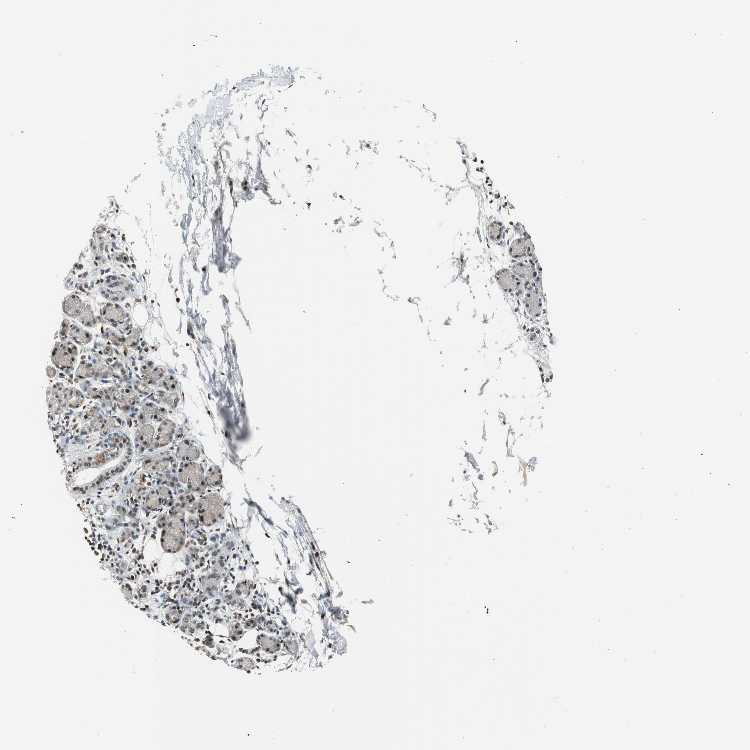

SOFT TISSUE 1 - Antibody stainingi

Antibody staining in the annotated cell types in the current human tissue is reported as not detected, low, medium, or high, based on conventional immunohistochemistry profiling in selected tissues. This score is based on the combination of the staining intensity and fraction of stained cells.

Each image is clickable and will lead to virtual microscopy that enables deeper exploration of all samples and also displays staining intensity scores, fraction scores and subcellular localization as well as patient and tissue information for each sample.

SOFT TISSUE 2 - Antibody stainingi

Antibody HPA005653

Fibroblasts Low

Peripheral nerve Not detected